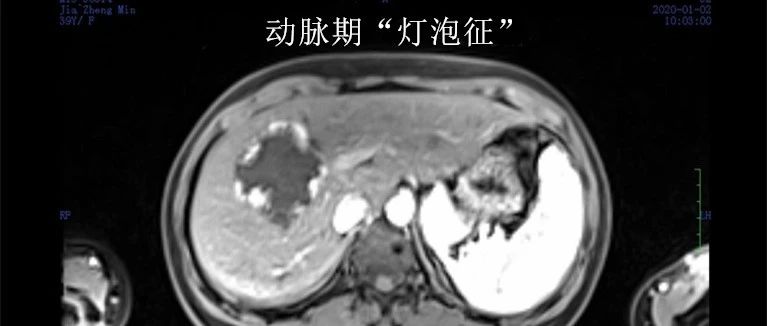

肝血管瘤——其实没那么恐怖​

如果血管瘤超过5 cm并且伴有症状,就应考虑治疗。

肝血管瘤——其实没那么恐怖